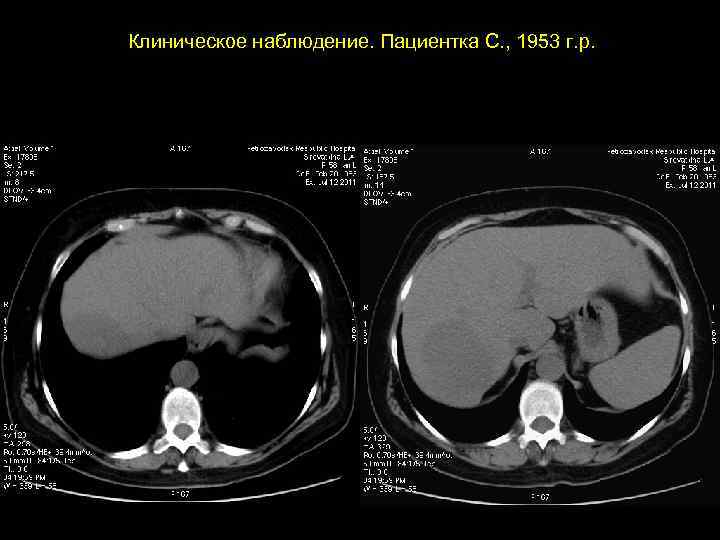

Клиническое наблюдение. Пациентка С. , 1953 г. р.

АКТУАЛЬНЫЕ ВОПРОСЫ РЕНТГЕНОЛОГИИ ЛУЧЕВАЯ ДИАГНОСТИКА ОЧАГОВЫХ ПОРАЖЕНИЙ ПЕЧЕНИ КАВЕРНОЗНАЯ ГЕМАНГИОМА Компьютерно-томографическая семиотика: - ограниченный участок пониженой плотности (до 50 -30 ед Н) - границы могут быть ровными, но нечеткими - после введения РКВ - характерный феномен усиления плотности от периферии к центру в течении нескольких минут после внутривенного введения РКВ